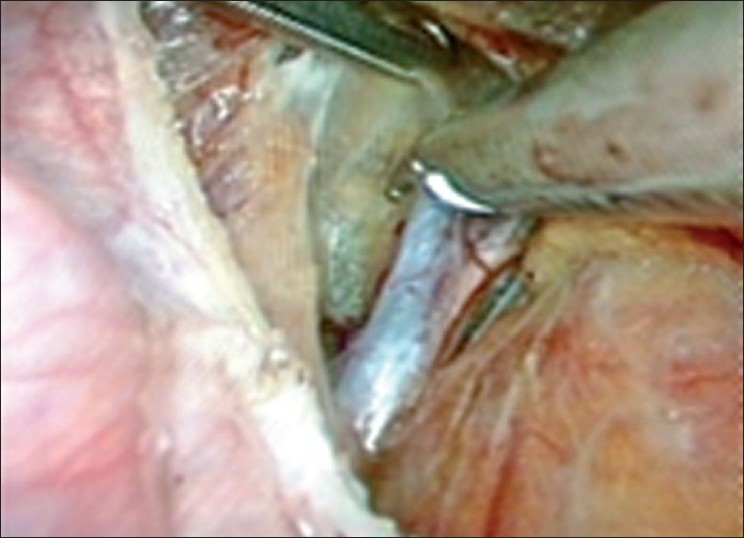

Most of the surgeons find it difficult to perform myomectomy when it bleeds during the procedure as it becomes difficult to get into the correct plane of dissection. If this bleeding or blood staining of tissues is prevented it will be easier to get into the correct plane of dissection. In several studies, it is found that bilateral uterine artery ligation, at origin, does not interfere with future fertility as the end vessels and collaterals of the uterus are not interfered with. As no energy source is used to incise the myoma once Vasopressin has been used, the myomectomy scar integrity is better, as noted by various surgeons.